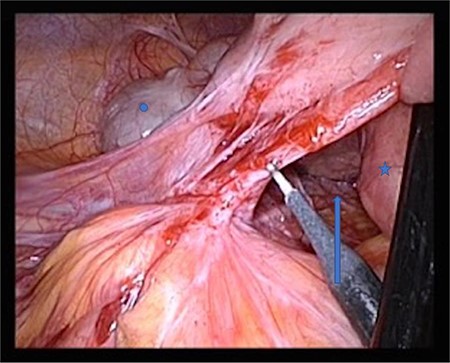

The patient was positioned supine. We used a 12-mm umbilical camera port, and 5-mm trocars were placed in the left and right middle abdomen. Laparoscopic inspection revealed a hernia aperture below the terminal ileum, behind which we found the hernia sac where the small intestine had become entangled 3 weeks previously (Fig. 3). The subsequent small bowel revision was uneventful. In the area of Treitz’s ligament, the vessels were on the right side with no herniation on the left side (Fig. 4). At this point, we decided to enlarge the hernia aperture by mobilizing the cecum. The ureter and the testicular vessels were identified. Finally, the hernia sac was widened, to prevent future entrapment of the small intestine. (Fig. 5) The postoperative course was uneventful and the patient was discharged 2 days later.

Star: transverse colon under the greater omentum, arrow: vessel axis, circle: proximal jejunum. The ligament of Treitz is not shown